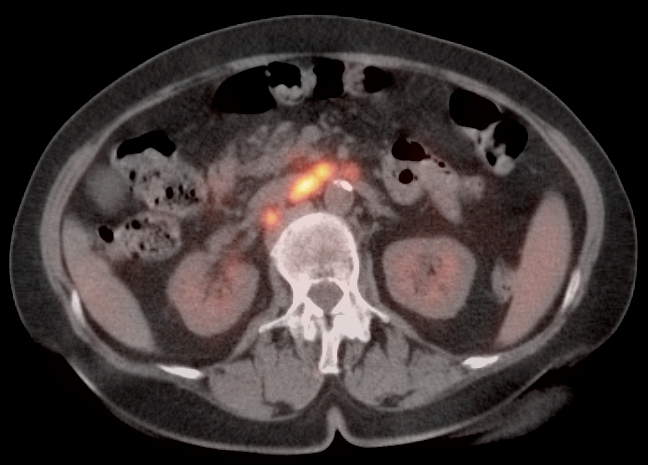

• Valuable diagnostic tool for locally advanced disease, to determine nodal status and potential distant metastatic disease (if no evidence of regional or distant disease, initial management is surgical).

• PET/CT has high sensitivity (>80%) and high specificity (>90%) for metastatic lymph nodes ≥ 8.0 mm.

• Lymphatic spread to pelvic and retroperitoneal lymph nodes.